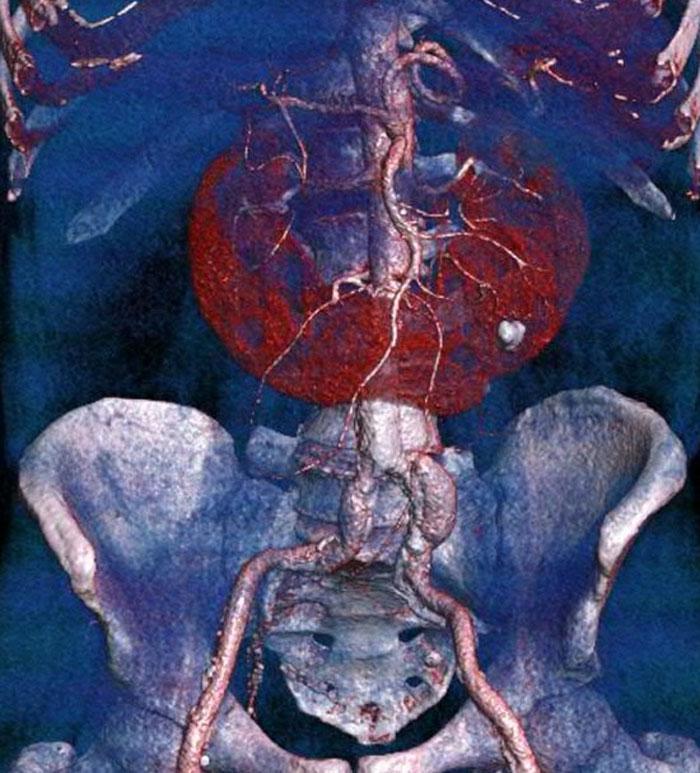

A massive aortic dissection. The woman's aorta was enormous, wider than a garden hose. EDIT: I meant a fire hose lol.

Image credits: Anoia_The_Anancastic